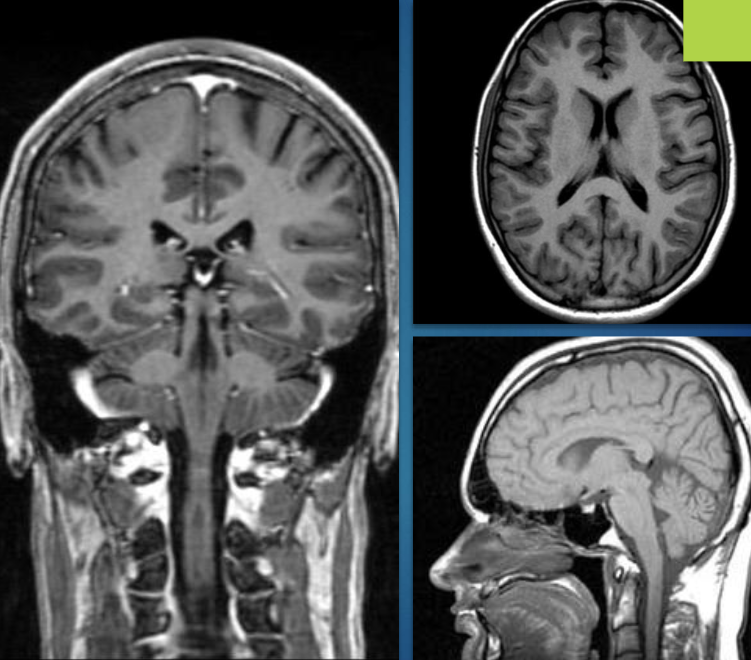

what is MRI?

radiation free medical imaging technique that uses powerful magenetic fields (10,000-60,000) times stronger than earth’s magnetic field

how does MRI work?

it uses the magnetic resonance properties of protons

nucleus of hydrogen atom (which are abundant in biological tissues)

produces 3D detailed images